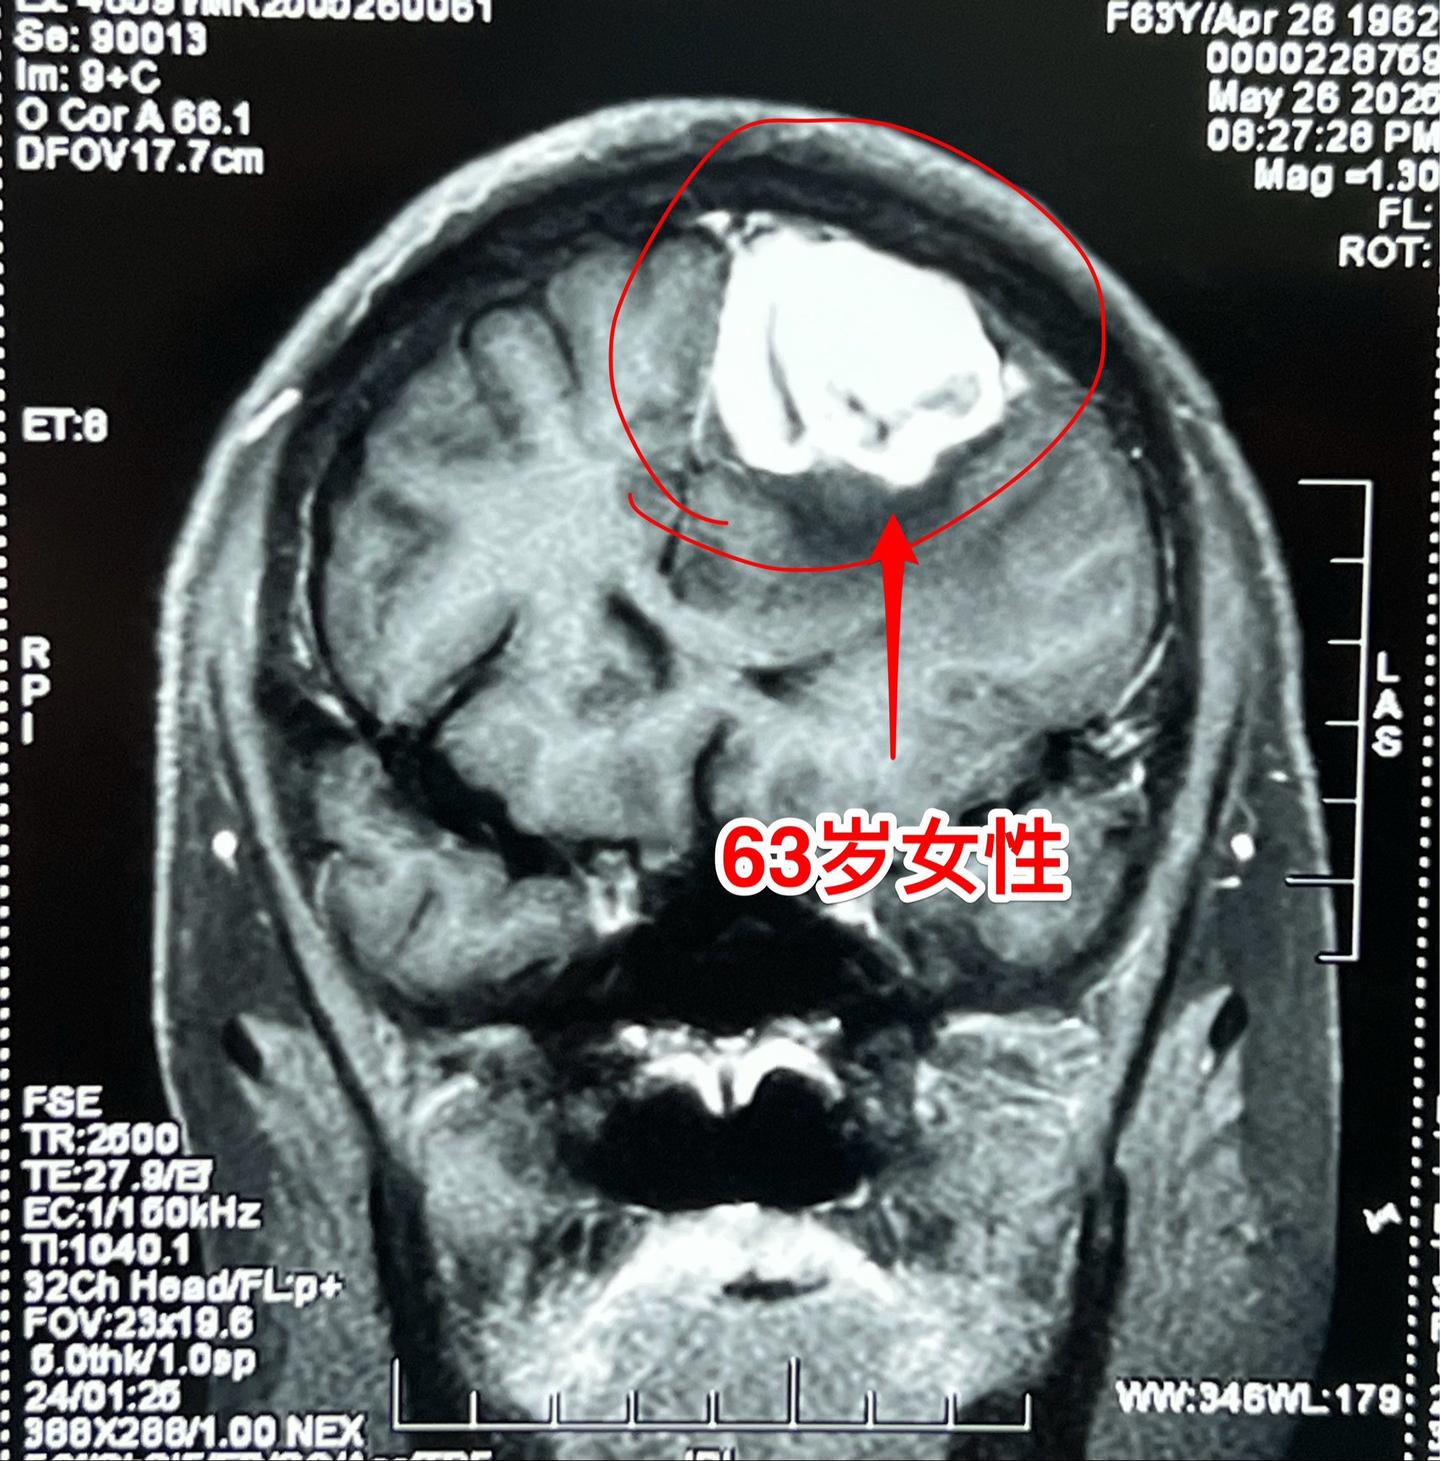

患冠心病、脑梗塞后又发现脑肿瘤。63岁随州女性,之前曾经患冠心病,作过心脏搭桥手术。也曾患过脑梗塞。幸运的是经过治疗,她没有明显的后遗症,可以在家做家务,还能下地干农活儿。 大约2周前病人出现头痛、精神差,随后出现右腿无力,行走时摔了一跤,病情越来越严重。 磁共振显示左侧额部有一个肿瘤,肿瘤周围有大面积水肿,胶质瘤?或者是别的肿瘤? 昨晚(5.30)为她作了手术,肿瘤得到整块切除。病人在手术后四肢活动无障碍。三个工作日后病理结果会出来的,后续的治疗需要根据病理诊